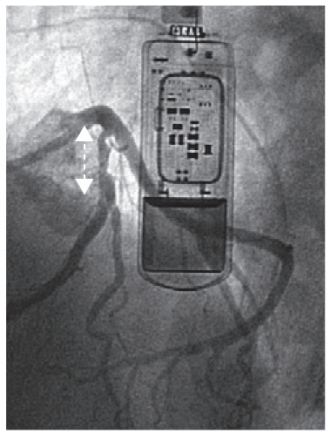

1个月后,患者在出现1次先兆晕厥发作后,紧急入住心内科。ILR的记录显示了ST段压低的非持续性室颤(附图A)。这一发现提示了无症状缺血诱发心律失常的可能性。急行冠状动脉造影显示左前降支(LAD)存在有临床意义的狭窄(附图B)。

B. 冠状动脉造影图像(血管造影显示LAD狭窄[箭头]和ILR设备)